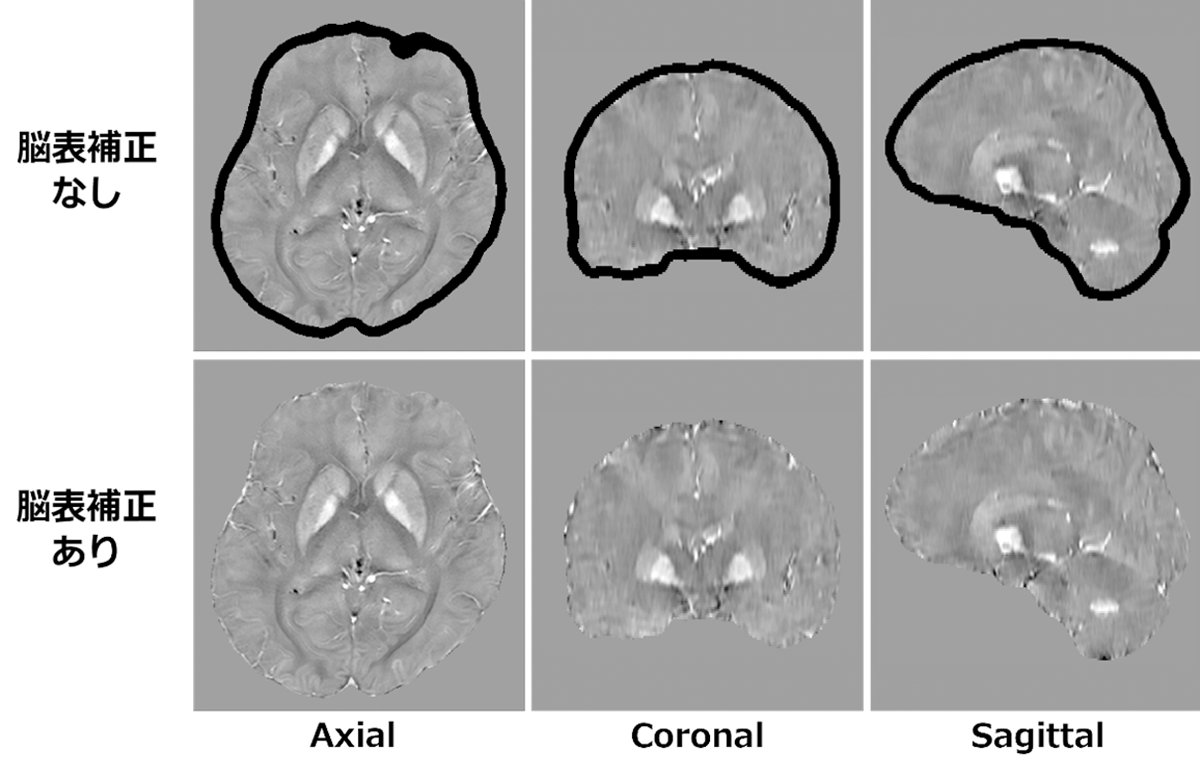

従来のQSM処理では、脳表領域の位相変化の算出精度が低下するため、脳表領域のQSMを算出することができませんでした3) (図7上段)。SYNAPSE VINCENT Coreでは、絶対値画像と位相画像から磁化率の差を画像化する際に脳表領域を含む脳全体の位相変化を画像処理で補正する技術を適用しました4)。これにより、脳表領域を含んだQSMを算出することができます*9(図7下段)。

図7 脳表補正有無によるQSMの違い